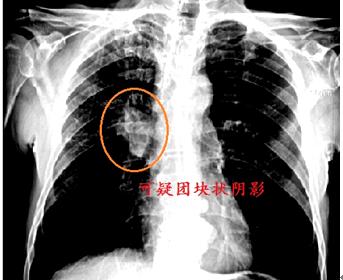

理想的肿瘤标志物是同时具有:特异性强(单一针对某种癌症),灵敏度高(在癌症极早期即升高),数值变量与肿瘤大小或侵袭性呈正相关的特点。但在现实中我们还远不能达到以上理想的标准。因此肿瘤标记物的结果并非“金标准”,其存在假阴、阳性的可能。因此在操作时,医生会尽量使用多项肿瘤标记物联合检测,且配合影像学、病理学、细胞学同时对肿瘤进行诊断,以利用其优势,规避其缺陷。